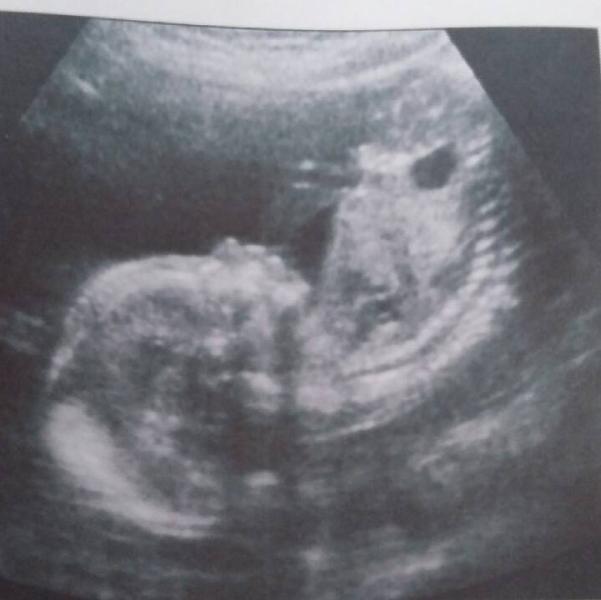

Сходили на платное УЗИ в "Optimus", нам ровно 20 нед. Мы 17см. и 418гр. Врач очень хорошая, все объясняла и показывала, не то что на коломенской. В общем отличный центр всем советую.

@sweetlove, сынок у нас будет, хоть и хотели девочку все равно безумно рады)))

обожаю фото с узи, когда носик, щёчки видно, что бы кто не говорил, все детки такие разные! прелесть просто:))